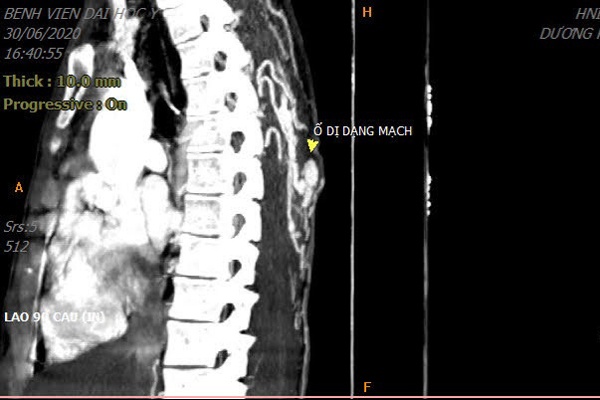

Hình ảnh búi dị dạng tập trung phía sau lưng bệnh nhân. Ảnh: BVCC.

Sau thăm khám lâm sàng và chụp chiếu, các bác sĩ phát hiện nằm ẩn phía dưới vết chảy máu ngoài da là một khối dị dạng mạch rất lớn. Búi thông động tĩnh mạch lan tỏa dưới da và trong cơ lưng với động mạch đi vào ổ dị dạng tách trực tiếp từ động mạch chủ ngực.

Do áp lực dòng chảy lớn nên phần nằm nông dưới da của ổ dị dạng to dần theo thời gian khiến bệnh nhân tưởng nhầm là mụn. Khi dùng sức nặn, ổ dị dạng bị vỡ, tạo áp lực gây chảy máu không cầm.